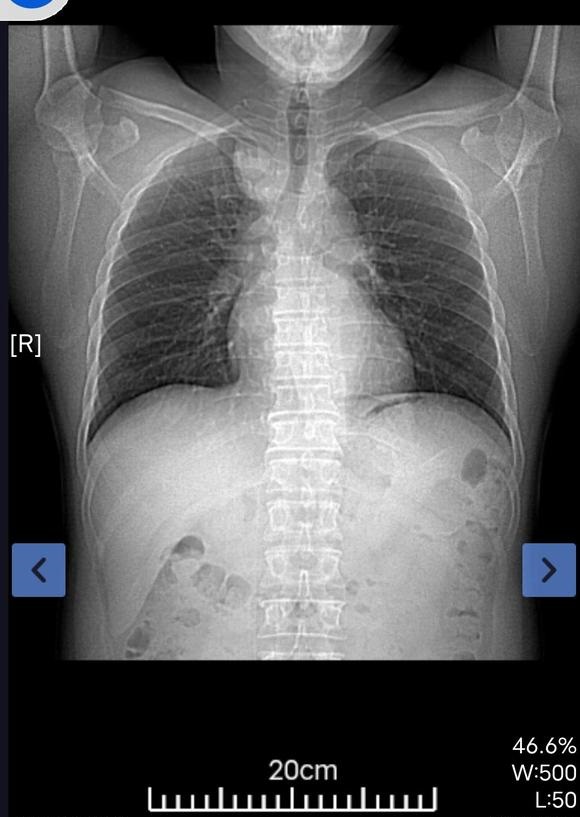

躺活,也是一种活 02022-05-31 患者那时,我也是被判了死刑,医生都要我家人放弃,可是我挺过来了,那时发现时已经10.5*7.5了,中心型肺癌,纵隔淋巴结转移...